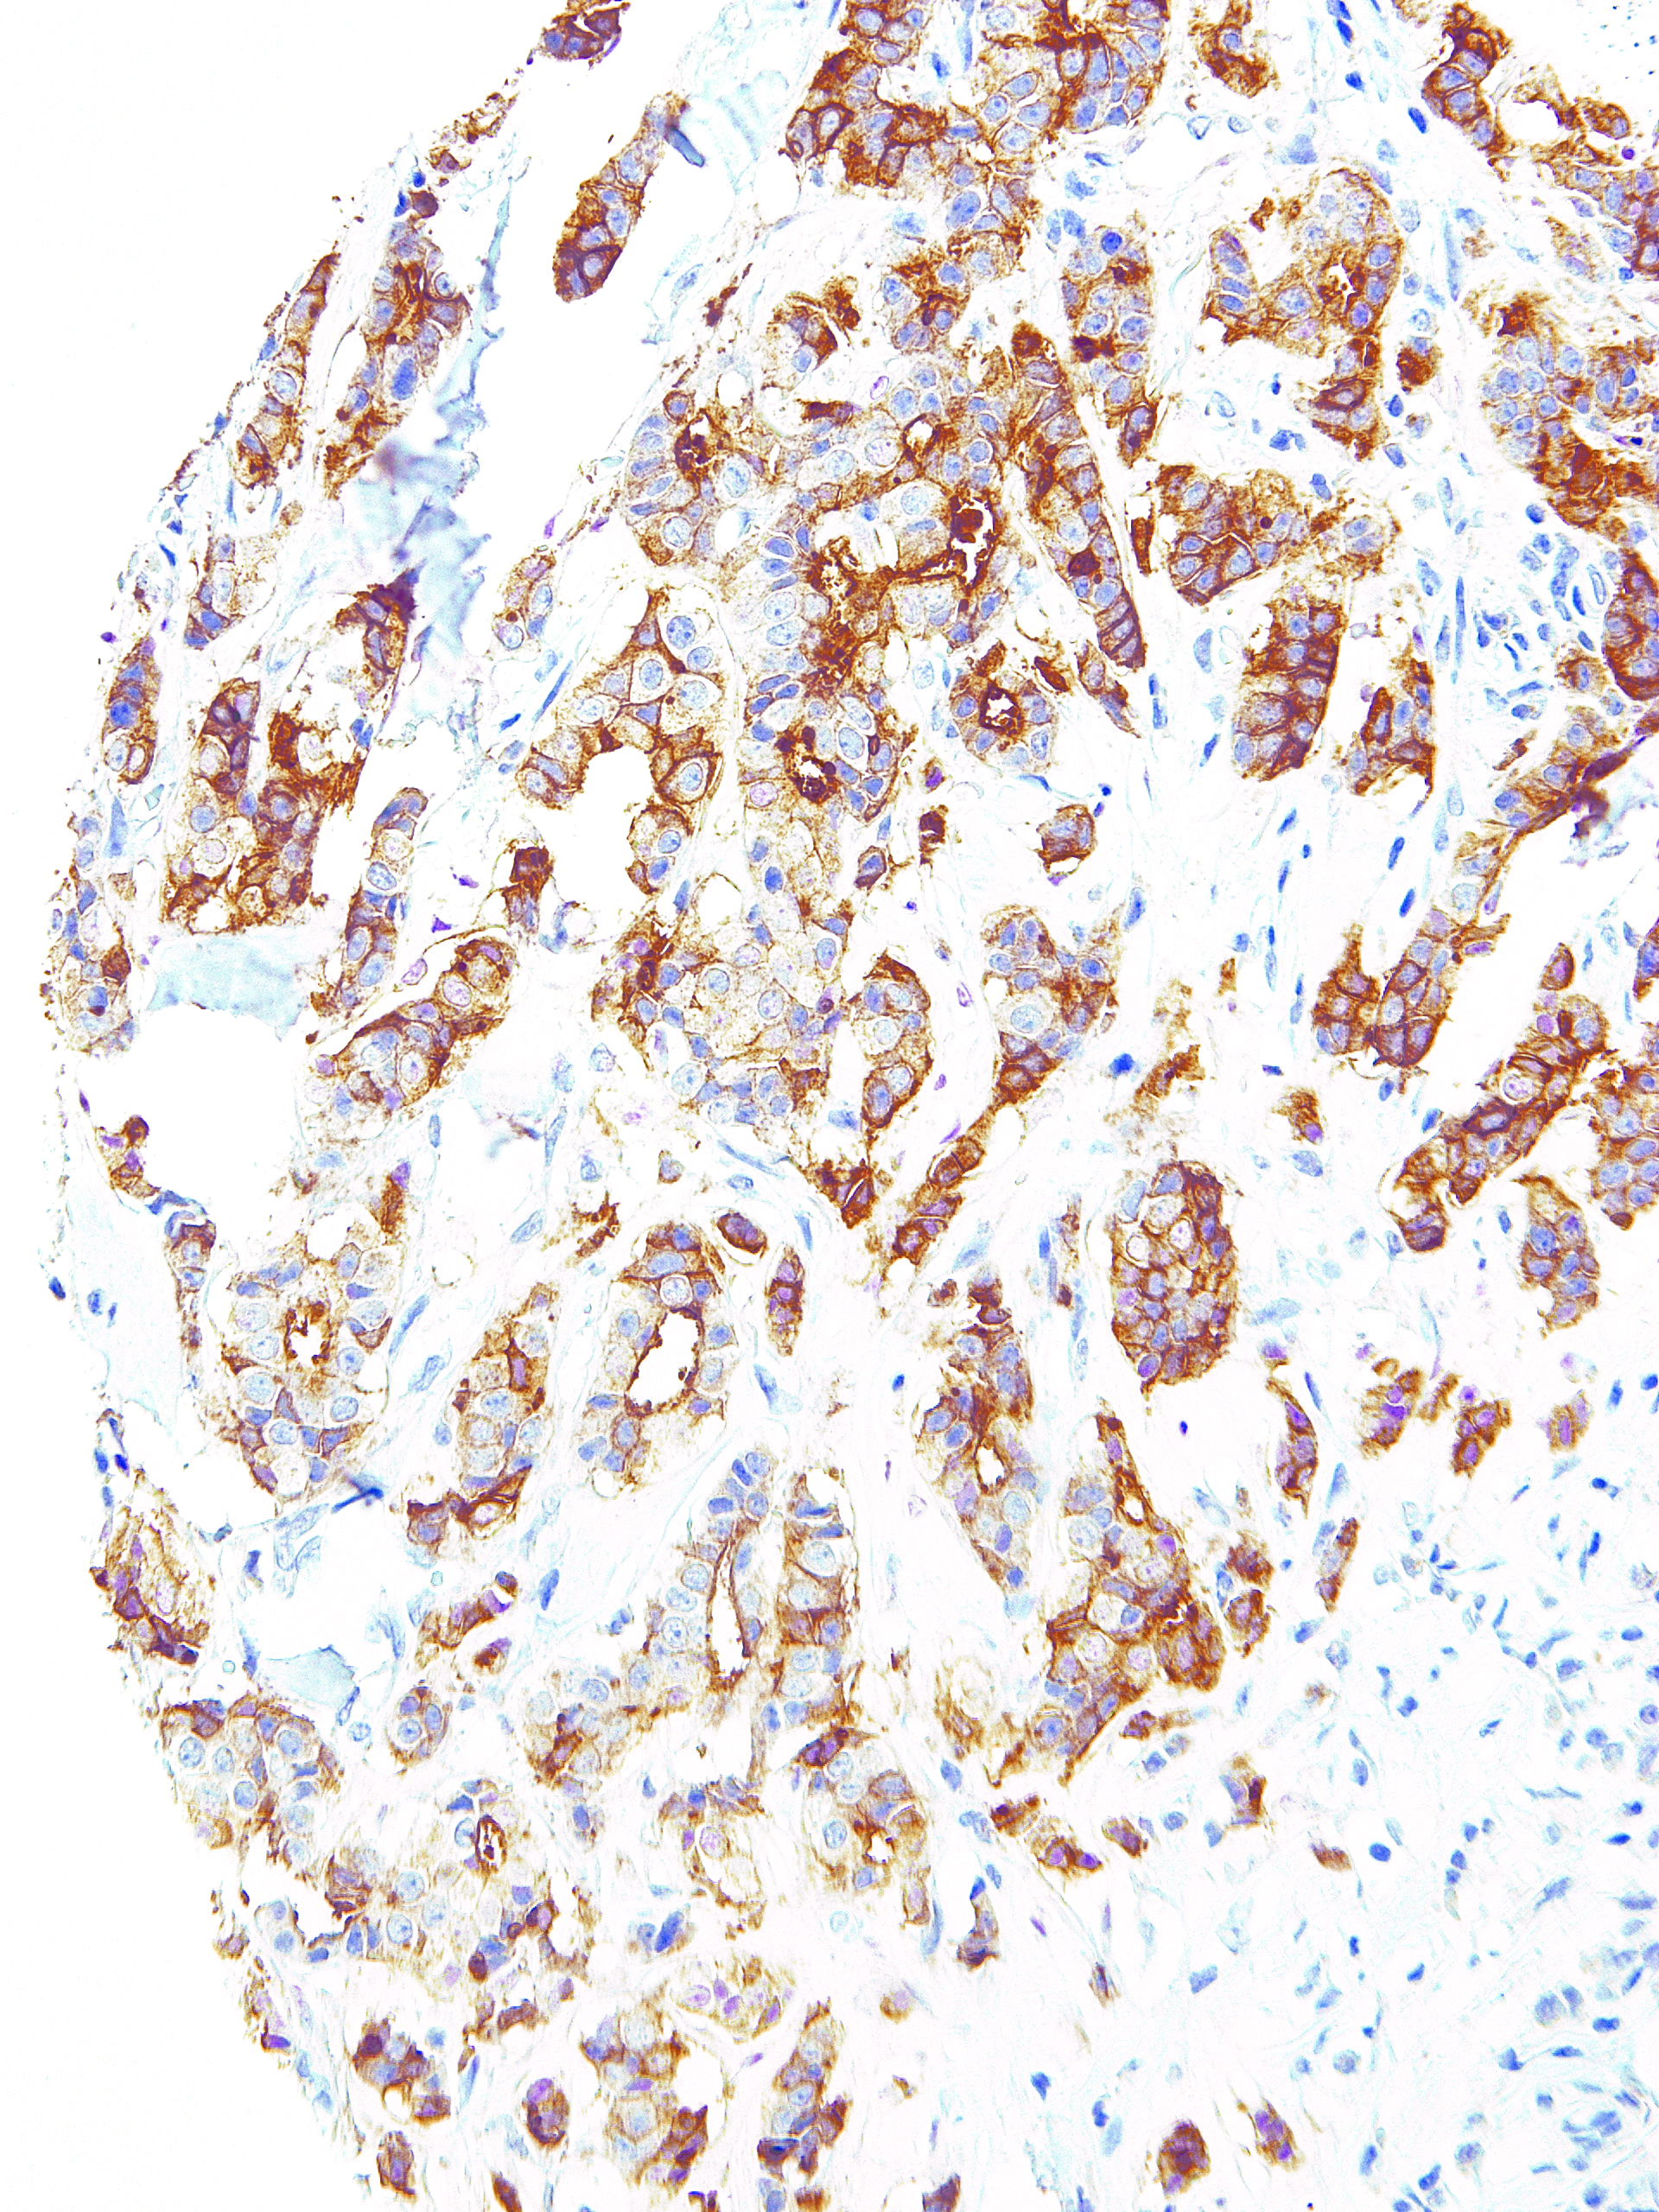

[Genomeme] B7-H4

CAT. NO. IHC104-100

POSITIVE CONTROL:

Breast

B7-H4 is a glycosylated transmembrane protein of the B7 family. It binds to activated T cells to moderate the T cell responses via cell cycle arrest in the T cell. Reverse signaling can induce either cell cycle arrest or apoptosis in the B7-H4 expressing cell. B7-H4 is up-regulated in several carcinomas in correlation with tumor progression and metastasis. A soluble form of B7-H4 is elevated in the serum of ovarian cancer, renal cell carcinoma, and rheumatoid arthritis patients, also in correlation with advanced disease status.